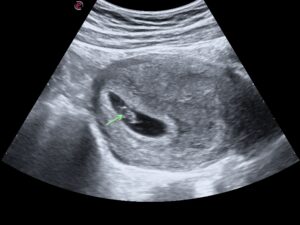

4-5 weeks

At 4-5 weeks after the 1st day of the last menstrual period, we can only see a small gestation sac. (The fetus will not be visible as yet)

At approximately 5 -6 weeks, we start to see the yolk sac in the gestation sac.